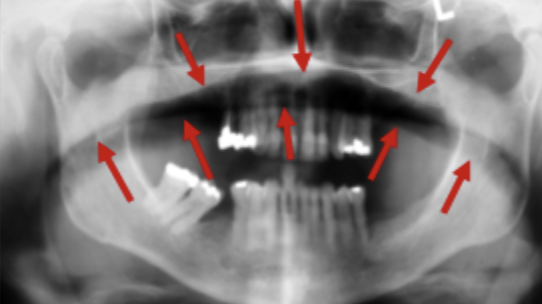

Panoramic indications

Treatment planning

Ortho → Check presence/absence of teeth

Implant planning → Assess vertical bone height

3rd molar extraction → Position/condition before surgert.

Assessment/diagnosis

Poor oral condition (after clinical exam)

Unerupted teeth/bone formation not seen in intraorals.

Perio evaluation, pockets <5mm.

Mandibular fractures

Maxillary sinus pathologies (basr, posterior, lateral walls)

Analyzing OPG

PT age & gender

Age characteristics

Panoramic image → position & image formation.

Anatomical local. of lesion

Size, shape, borders & contours.

Lesion structure → opaque, lucent, mixed.

Effect on adjacent structures.